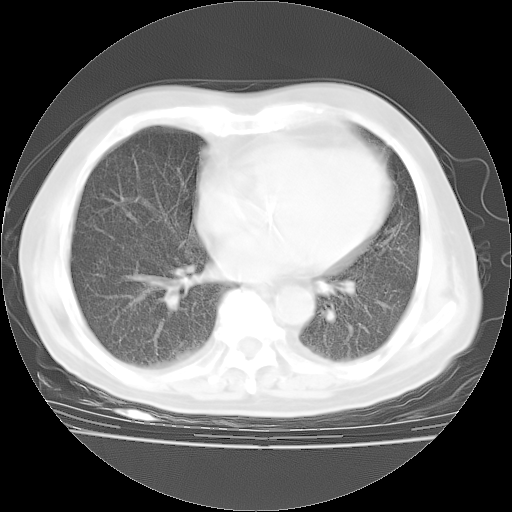

4月28日肺部CT——再次出现类似去年5月9日——透光度降低,“间质性”改变。

4月28日肺部CT——再次出现类似去年5月9日——磨玻璃样、间有“粟粒样”改变。

4月28日肺部CT

个人阅读4.14日肺部CT平扫:纵隔窗无异常,但肺窗示:双下肺内、后基底段有片絮状侵润影,部位以后基底段为著,以间质改变为主,呈急性肺泡炎征像,和首次住院影像学有相似之处。仅是个人读片,明日请相关专家再读片哈。其它建议同上。